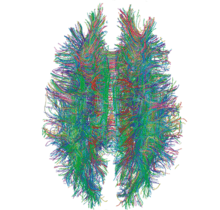

Diffusion MRI

Diffusion MRI measures the diffusion of water molecules in biological tissues.[161] Clinically, diffusion MRI is useful for the diagnoses of conditions (e.g., stroke) or neurological disorders (e.g., multiple sclerosis), and helps better understand the connectivity of white matter axons in the central nervous system.[162] In an isotropic medium (inside a glass of water for example), water molecules naturally move randomly according to turbulence and Brownian motion. In biological tissues however, where the Reynolds number is low enough for laminar flow, the diffusion may be anisotropic. For example, a molecule inside the axon of a neuron has a low probability of crossing the myelin membrane. Therefore, the molecule moves principally along the axis of the neural fiber. If it is known that molecules in a particular voxel diffuse principally in one direction, the assumption can be made that the majority of the fibers in this area are parallel to that direction.

The recent development of diffusion tensor imaging (DTI)[163] enables diffusion to be measured in multiple directions, and the fractional anisotropy in each direction to be calculated for each voxel. This enables researchers to make brain maps of fiber directions to examine the connectivity of different regions in the brain (using tractography) or to examine areas of neural degeneration and demyelination in diseases like multiple sclerosis.